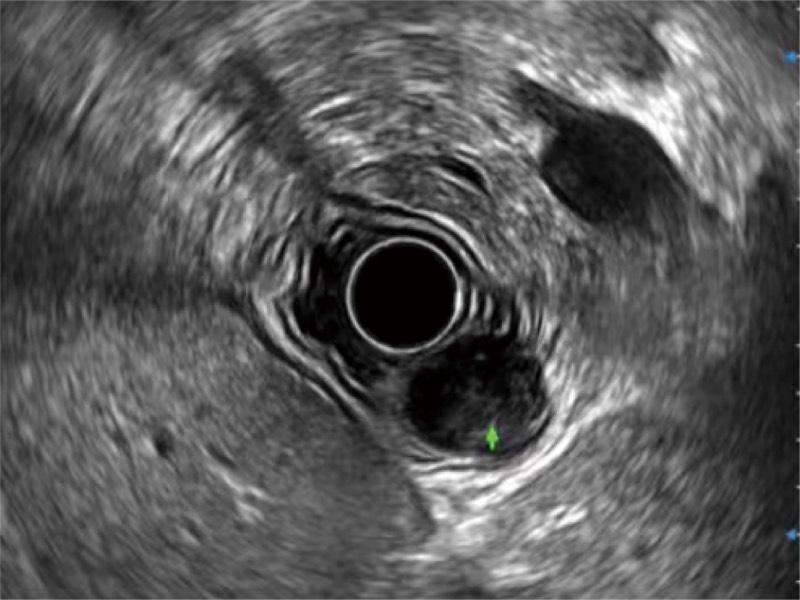

微米成像技术提升了对组织斑点噪声信号的抑制能力,并进一步强化边界信息,从而获得信噪比更优、边界更清楚锐利的图像

随着组织深度的变化,超声接收频率进行智能匹配跟踪,确保图像中、远场良好的穿透力以及整场一致的分辨力,从而得到均一的画质

食管内间质瘤清晰显像